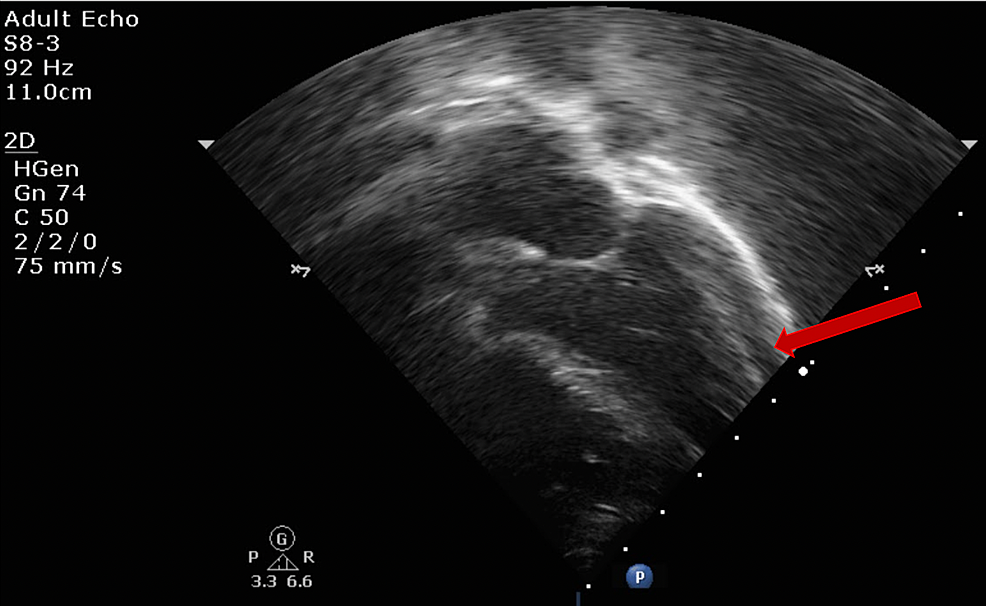

This study did not require approval from the Ethics Committee. The data that support the findings of this study are available from the corresponding author, upon reasonable request. Longitudinal follow-up showed improvement in all of these findings, with resolution of most by early follow-up. The TTE findings in patients with MIS-C are striking and fit a clear pattern of systemic inflammation and pancarditis that includes holodiastolic reversal of flow in the descending aorta, LV systolic dysfunction, LV diastolic dysfunction, CA abnormalities, valvar dysfunction, and pericardial effusion. This is the first report to describe all of the abnormal features of the TTE during the acute phase of MIS-C, with the findings suggestive of a pancarditis, arteritis, and systemic inflammatory response similar to that seen in KD.

The TTE findings in patients with MIS-C are striking and fit a pattern that includes holodiastolic reversal of flow in the descending aorta, LV systolic dysfunction, LV diastolic dysfunction, CA abnormalities, valvar dysfunction, and pericardial effusion. Twenty six percent were Hispanic, and the racial breakdown was as follows: 42% multiracial, 30% Black, 8% White, 12% Discussion The mean age was 8.3 years (range 9 months to 17 years). Data collectionįifty patients were admitted to our hospital between Maand Jand met the CDC criteria for MIS-C 45 patients (90%) were positive for serum SARS-CoV-2 IgG antibodies, 13 patients (26%) were positive by nasopharyngeal PCR, and 8 (16%) patients were positive for both. Patients in this study were also included in publications from other investigators from our institution. This is a retrospective single center study that includes consecutive pediatric patients age ≤ 18 years who were admitted to Cohen Children's Medical Center (Northwell Health) from Mato Jwith laboratory-confirmed SARS-CoV-2 infection by respiratory polymerase chain reaction (PCR) testing and/or IgG serology and met CDC criteria for MIS-C.

Few reports have noted the incidence of valvar regurgitation and/or pericardial effusion, with one study of 12 patients reporting small effusions in 33%, mild or greater mitral regurgitation (MR) in 25%, and mild or greater tricuspid regurgitation (TR) in 17%. While CA dilation and LV dysfunction are extremely important, they do not comprise the entirety of the cardiac involvement that can be seen with transthoracic echocardiography (TTE). CA aneurysms range in incidence from 14 to 24% and LV systolic dysfunction has been reported in 31% to 58%. There have been multiple reports on coronary artery (CA) dilation and left ventricular (LV) systolic dysfunction in MIS-C. Multisystem inflammatory syndrome in children (MIS-C) has been described as a post-inflammatory condition associated with Coronavirus Disease 2019 (COVID-19) with a range of clinical features, including cardiac manifestations similar to Kawasaki disease (KD), ,.